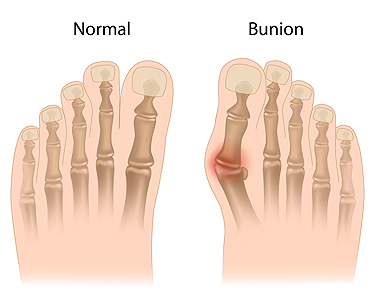

What Can Be Done to Treat Bunions?

Bunions are bony growths that appear along the outside of the foot at the base of the big toe joint. They are thought to occur in response to excess pressure and friction on the toes from wearing ill-fitting shoes, as well as due to a genetic predisposition for bunions. This common toe deformity can be painful, as the bunions rub against shoes and cause the big toe to move out of alignment and towards the smaller toes. There are a variety of treatment methods available for bunions. Conservative methods can be prescribed to manage the symptoms of a bunion. These may include wearing wider, more supportive shoes, wearing orthotics such as toe stretchers, splints, or bunion pads, taking over-the-counter medications to reduce pain, and applying ice to the bunion to decrease inflammation. Bunions can be removed permanently through surgery. If you have painful bunions, talk to your podiatrist about potential treatment options today.

What Is a Bunion?

A bunion is formed of swollen tissue or an enlargement of boney growth, usually located at the base joint of the toe that connects to the foot. The swelling occurs due to the bones in the big toe shifting inward, which impacts the other toes of the foot. This causes the area around the base of the big toe to become inflamed and painful.

Bunions

A bunion is an enlargement of the base joint of the toe that connects to the foot, often formed from a bony growth or a patch of swollen tissues. It is caused by the inward shifting of the bones in the big toe, toward the other toes of the foot. This shift can cause a serious amount of pain and discomfort. The area around the big toe can become inflamed, red, and painful.

Bunions are most commonly formed in people who are already genetically predisposed to them or other kinds of bone displacements. Existing bunions can be worsened by wearing improperly fitting shoes. Trying to cram your feet into high heels or running or walking in a way that causes too much stress on the feet can exacerbate bunion development. High heels not only push the big toe inward, but shift one's body weight and center of gravity towards the edge of the feet and toes, expediting bone displacement.

A podiatrist knowledgeable in foot structure and biomechanics will be able to quickly diagnose bunions. Bunions must be distinguished from gout or arthritic conditions, so blood tests may be necessary. The podiatrist may order a radiological exam to provide an image of the bone structure. If the x-ray demonstrates an enlargement of the joint near the base of the toe and a shifting toward the smaller toes, this is indicative of a bunion.

Wearing wider shoes can reduce pressure on the bunion and minimize pain, and high heeled shoes should be eliminated for a period of time. This may be enough to eliminate the pain associated with bunions; however, if pain persists, anti-inflammatory drugs may be prescribed. Severe pain may require an injection of steroids near the bunion. Orthotics for shoes may be prescribed which, by altering the pressure on the foot, can be helpful in reducing pain. These do not correct the problem; but by eliminating the pain, they can provide relief.

For cases that do not respond to these methods of treatment, surgery can be done to reposition the toe. A surgeon may do this by taking out a section of bone or by rearranging the ligaments and tendons in the toe to help keep it properly aligned. It may be necessary even after surgery to wear more comfortable shoes that avoid placing pressure on the toe, as the big toe may move back to its former orientation toward the smaller toes.